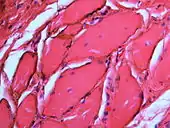

Over time, the amalgam particles embedded in the soft tissues corrode.[5]: 183 Macrophages take up the exogenous particles, and the silver in amalgam leads to staining of collagen fibers.[5]: 183

If necessary, the diagnosis can be confirmed histologically by excisional biopsy, which excludes nevi and melanomas.[3]: 138 If a biopsy is taken, the histopathologic appearance is:[1]

- Pigmented fragments of metal within connective tissue

- Staining of reticulin fibers with silver salts

- A scattered arrangement of large, dark, solid fragments or a fine, black or dark brown granules

- Large particles may be surrounded by chronically inflamed fibrous tissue

- Smaller particles surrounded by more significant inflammation, which may be granulomatous or a mixture of lymphocytes and plasma cells